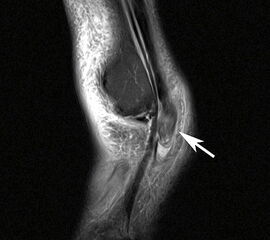

MRT mit KM bei Split der Peronaeus brevis Sehne in Höhe der Fibulaspitze

Abbildung 13

Klassischerweise beginnt eine Peronealsehnenruptur mit einem Distorsionstrauma. Bei dieser Verletzung kommt es zunächst zu einer Längsruptur (Peroneus-Split) der Peronaeus brevis Sehne in Höhe der Fibulaspitze. Bestehen nun Risikofaktoren wie eine persistierende Instabilität des Sprunggelenks oder ein bis zu diesem Zeitpunkt asymptomatischer Rückfußvarus, kommt bei jeder weiteren Distorsion zu einer Zunahme des Sehnenschadens bis hin zur vollständigen Kontinuitätsunterbrechung 38. Für das Peronaeus Split Syndrom gibt es kein klassisches Leitsymptom. Wichtig ist bei anhaltenden Beschwerden nach einem Distorsionstrauma an diese Differentialdiagnose zu denken und ein MRT mit Kontrastmittel zu veranlassen 39.